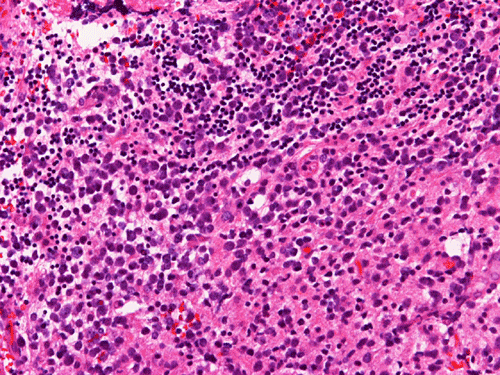

The material for permanent sections is largely semi-liquid in consistency. There are only very few fragments of cerebellar tissue that are infiltrated by the tumor. The bulk of the diagnostic material are solid sheets of neoplastic cells (Panel G). The cytologic features are similar to what we have observed in the cytologic preparation  (Panel H). In essence, the tumor is composed of solid sheets of large polygonal and rather monotonous atypical cells with a thin rim of cytoplasm and molding which lead to a mosaic pattern. These features are consistent with lymphoma. On immunohistochemistry, practically all the neoplastic cells are positive for leukocyte common antigen (LCA) (Panel I), CD20 (Panel J) and many of them are positive for CD79a (Panel K). Only reactive T-cells but not the large, atypical cells are positive for CD3 (Panel L). The neoplastic cells are essentially negative for Bcl-6 (Panel M) but some of them are positive for Bcl-2 (Panel N). The large atypical cells are negative for kappa and lambda light chains on immunohistochemistry. There is no immunoreactivity in the neoplastic cells for cytokeratin (AE1/AE3), S100, pan-melanoma marker (Mart-1, tryptase, and HMB-45).

Similar to the systemic counterparts, diffuse large-B cell lymphomas of the CNS are characterized by large, pleomorphic lympyoid cells. Histologically, however, PCNSL shows the unique angiocentric infiltrating pattern, which is more prominent at the edge of the lesion. The tumor cells dissect and expand the perivascular network in a concentric manner which is best demonstrated by reticulin stain

[click here to see a picture]. Systemic DLBCL does not show this particular pattern of growth. The tumor infiltrates the brain parenchyma between blood vessels as small clusters and individual cells. Confluent areas of tumor may show necrosis, with residual viable tumor cells being found mostly around blood vessels. The boundary of the tumor may be relatively discrete, but it is more common for perivascular cuffs and single infiltrating lymphoma cells to be found at some distance from the tumor mass, extending far away from radiographically evident tumor margins. The malignant lymphocytes lack a cohesive appearance, do not form glands or other structures. The nuclei vary from round to indented or cleaved, and prominent nucleoli can be noted. The cells have only a small amount of basophilic cytoplasm. Variable numbers of mitotic figures and apoptotic cells are seen.